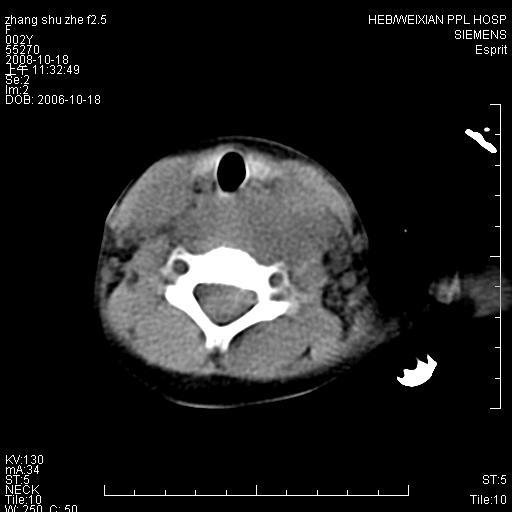

以下是引用dyqct在2009-2-10 21:04:00的发言:[br]年龄?性别?有发烧吗?[br]鼻咽部、口咽部、喉咽部及颈椎前间隙广泛肿厚,明显占位效应并致相应组织变形。ct值22-28hu。[br]考虑:1、颈前脓肿可能性大;[br] 2、建议增强或治疗后复查。

以下是引用jiangjing在2009-2-11 11:37:00的发言:[br]急性病程,鼻咽部、口咽部、喉咽部及颈椎前间隙广泛肿厚,明显占位效应并致相应组织变形.考虑颈部感染性病变(脓肿?);建议行进一步检查。